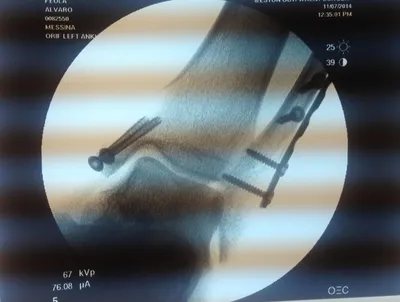

CT scan and Xray sagittal views of severly displaced posterior tibial malleolar fracture with comminution. This type of injury can cause significant problems in the future with disability if not treated with surgery to reduce the fracture and fixate.

Xray and CT scan of displaced medial and posterior malleolar fracture with ORIF